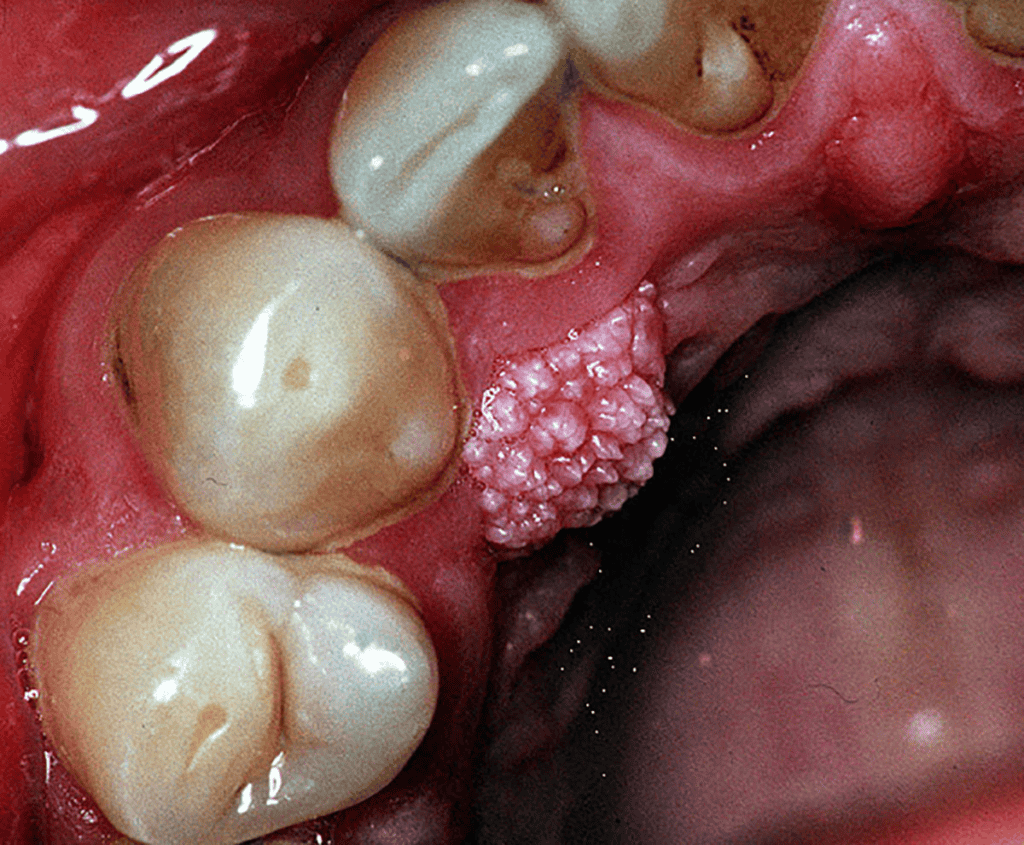

تصویر و شکل ظاهری زگیل تناسلی در دهان

زگیلهای دهانی در تصویر و معاینه بالینی ظاهری متفاوت دارند. برای شناخت بهتر این ضایعات، توصیف دقیق ویژگیهای ظاهری آنها ضروری است:

- رنگ: معمولاً همرنگ پوست، سفید، صورتی یا خاکستری است.

- شکل: ممکن است به شکل برجستگیهای کوچک و منفرد، خوشهای شبیه گل کلم، یا ضایعات مسطح دیده شوند.

- بافت: نرم، مرطوب و گاهی زبر.

- اندازه: از چند میلیمتر تا چند سانتیمتر متفاوت است.

- محل: روی زبان، داخل لبها، لثه، کام، لوزهها و ته حلق.

در بسیاری از موارد این زگیلها بدون علامت هستند و فرد مدتها بدون اینکه بداند ناقل ویروس است. به همین دلیل توجه به تصویر و ظاهر ضایعه اهمیت زیادی دارد، هرچند تشخیص قطعی حتماً باید توسط پزشک انجام شود.